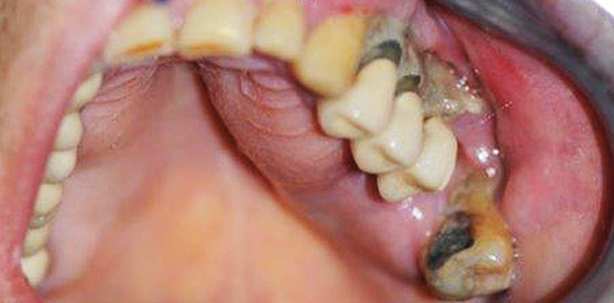

Der freiliegende Kieferknochen ohne Heilungstendenz stellt das Leitsymptom dar. Aus diesem Grund ist die Untersuchung der Mundhöhle für die primäre Diagnostik meist wichtiger als ein Röntgenbild. Oft sind die betroffenen Kieferareale trotz Nekrose nicht schmerzhaft, häufiger dagegen tritt ein merkbarer Mundgeruch auf. Das Röntgenbild kann für den Zahnarzt, Oral- oder MKG-Chirurgen wichtig werden, um nach einer Zahnentfernung die knöcherne Durchbauung zu kontrollieren (Ausschluss einer persistierenden Alveole) oder um die Ausdehnung ei- ner Nekrose für die OP-Planung zu bestimmen.

3. Therapie der BP-assoziierten Osteonekrose

Die Kiefernekrose ist schwierig zu therapieren, der Therapieverlauf zögerlich. Bei kleinen Befunden kann ein Therapieversuch mit begrenzter Abtragung und plastischer Deckung oder offener Nachbehandlung unternommen werden. Führt dies nicht zum Erfolg oder liegen ausgedehnte Befunde vor, ist eine schonende, aber vollständige Entfernung der Nekrose sowie das Abtragen scharfer Knochenkanten erforderlich. Sehr wichtig für den Heilverlauf ist eine sichere mehrschichtige plastische Deckung, oft unter Nutzung von Weichgewebe aus der Nachbarschaft. Nicht selten wird der Eingriff unter Vollnarkose vorgenommen. Dies und die Tatsache, dass oft ein Antibiotikum über die Vene gegeben wird und spezielle Kostformen die mechanische Wundbelastung reduzieren, erfordert nicht selten eine stationäre Behandlung in einer Klinik für Mund-Kiefer-Gesichtschirurgie.